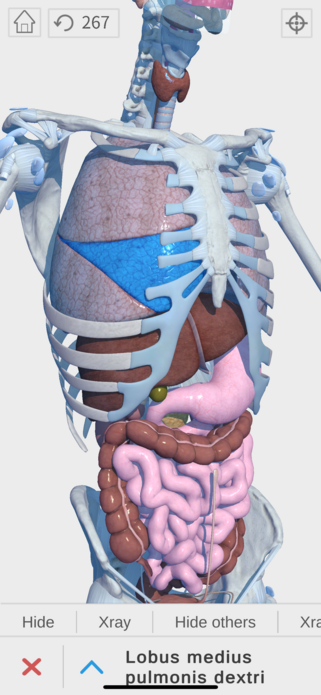

Complete and easy-to-use virtual guide for learning, understanding, and visualizing the complexities of human anatomy in 3D. Includes information and images for each anatomical system and part, multiple options to interact with the 3D anatomy models (hiding, fading, etc), and much more.

We believe that learning by interaction is the best and easiest way to study human anatomy.

- over 1200 body parts!

- highly detailed

- zoom, pan, and rotate in real time

- show and hide layers

- see details for each body part

Hi-res imagery everywhere you need it

- Digestive

- Respiratory